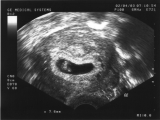

Wir haben unseren Nachwuchs entdeckt. Auf diesem Bild ist er gerade mal 5 Wochen alt.

Das Bild entstand am 19.03.03